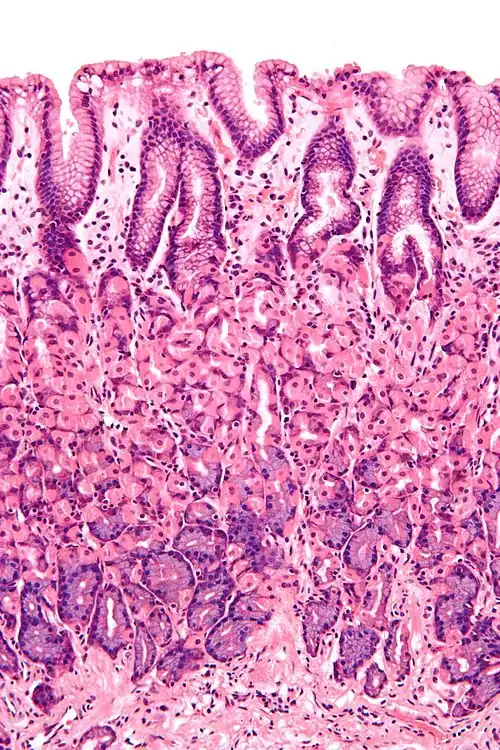

En el intestino delgado, las vellosidades (villi) son pliegues de la mucosa que aumentan la superficie de absorción del intestino. Cada vellosidad contiene el conducto lacteal o quilífero central que es una conexión al sistema linfático que ayuda en la extracción de los lípidos y fluidos desde el tejido. Sobre la superficie apical de cada enterocito están presentes las microvellosidades que son micro pliegues de la membrana celular que aumentan aún más la superficie de absorción.

Las numerosas glándulas intestinales son como invaginaciones, (con forma de bolsillo), que están localizadas en el tejido subyacente.

En el intestino grueso, las vellosidades (villi) están ausentes y se observa una superficie plana con miles de orificios de las glándulas.

- En el intestino delgado, el epitelio columnar es simple y especializado para la absorción. El epitelio está estructurado en plicas que contienen vellosidades, aumentando de esta forma el área para absorción. Cada célula tiene microvellosidades que forman un borde en cepillo que aumenta en gran medida la superficie disponible para la absorción. El epitelio es columnar simple con microvellosidades. En el íleon en ocasiones hay placas de Peyer en la lámina propia. Las glándulas de Brunner se encuentran en el duodeno, pero no en otras partes del intestino delgado[1]

- En el colon, el epitelio es columnar simple y sin vellosidades. Las células caliciformes, que secretan moco, también están presentes.